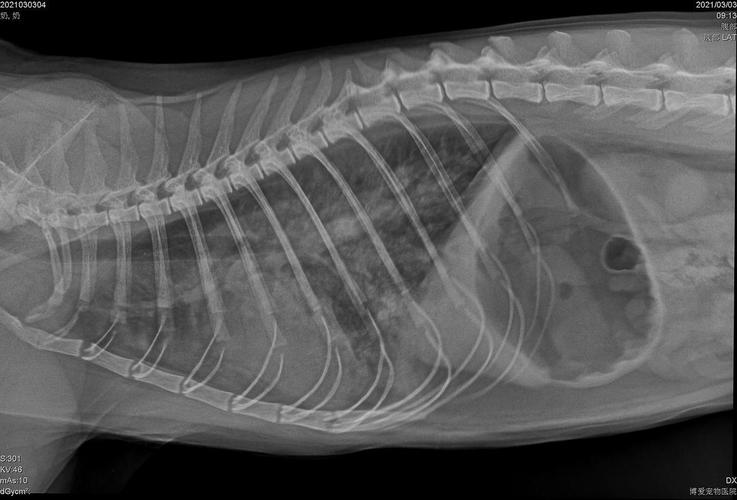

〖肆〗、猫咪肺水肿的常见症状有咳嗽、呼吸急促、呼吸困难、食欲下降等。另外,根据原发病因不同,猫咪出现的症状也不同。猫咪肺水肿的原因需要依靠X光片,以及结合病史、体格检查、超声心动图和生化检查等来确诊。根据病因不同,采用的治疗方法也不同。

猫咪肺水肿的常见症状有咳嗽、呼吸急促、呼吸困难、食欲下降等。另外,根据原发病因不同,猫咪出现的症状也不同。猫咪肺水肿的原因需要依靠X光片,以及结合病史、体格检查、超声心动图和生化检查等来确诊。根据病因不同,采用的治疗方法也不同。

猫肺水肿初期的症状一般有张口呼吸、呼吸急促、咳嗽、舌头发紫、不爱活动等,当猫咪出现疑似肺水肿的症状,建议带它就医拍X光片检查,肺水肿是会引起立即死亡的。

猫肺水肿初期症状:猫肺水肿在早期时的最明显症状就是频繁的咳嗽,而且还会出现呼吸紧促的情况,随着病情逐渐加重之后,就会出现呼吸困难、眼睑发干、胸部扩大,鼻腔当中以及气管当中也会有血色泡沫。当猫咪出现疑似肺水肿的症状,建议带它就医拍X光片检查,肺水肿是会引起立即死亡的。

猫咪肺水肿初期表现为:咳嗽、呼吸困难、喘息急促、眼睑和舌头发绀、胸部肿大、鼻腔、气管有血色泡沫等症状。猫咪患有肺水肿后会很快导致死亡,因此应立即送往宠物医院进行X光拍片检查,查看引起猫咪肺水肿的原因再对因治疗。